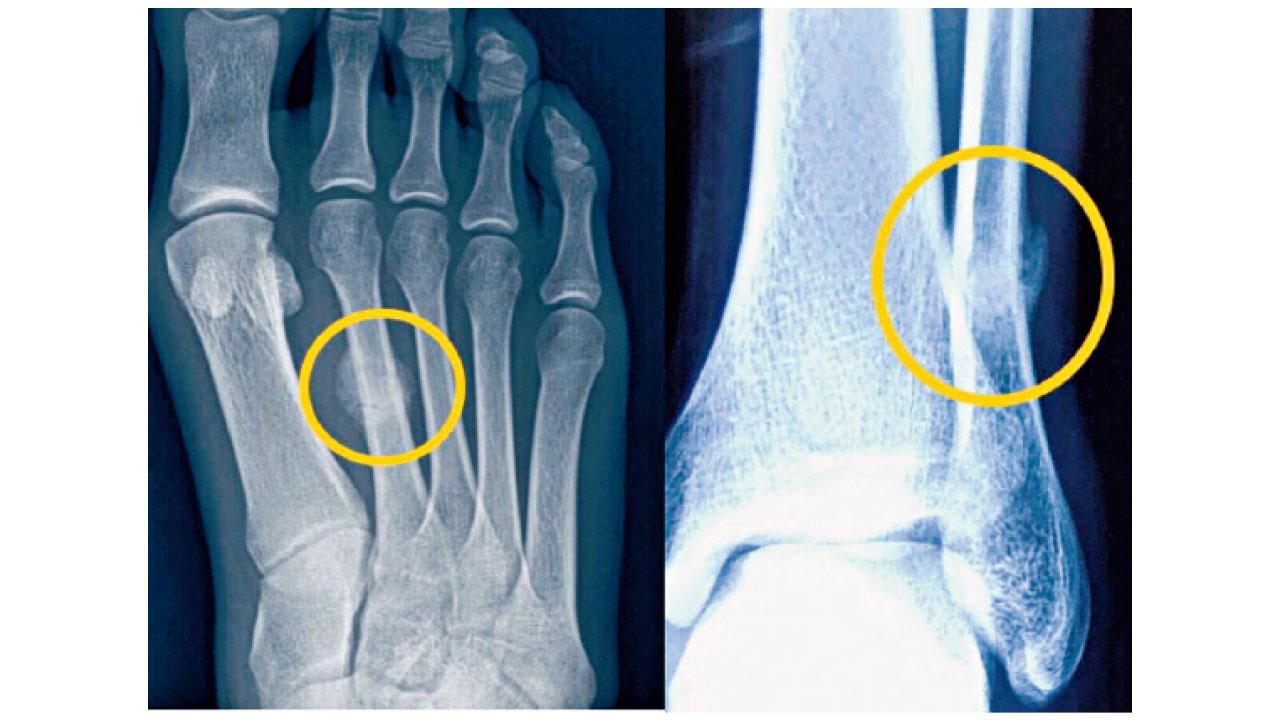

由於不少骨折患者會誤以為下肢痛楚,只是運動過後的肌肉痠痛或肌腱炎症,延誤求醫並不罕見。但即使在早期接受X光檢查,也較難察覺出明顯異常;及至數星期後的覆檢X光,才可照出骨折裂痕和骨外膜增生。因此就早期的疑似個案,最精準的診斷方法是照磁力共振。治療方面,大部分疲勞性骨折都屬於非移位且穩定的骨折,適合穿戴矯形器或打石膏來保護骨折至自然愈合,再配合止痛藥和物理治療促進復康進程。至於已移位或不穩定的骨折,例如是脛骨前側和股骨頸,便須接受內固定手術以防骨折愈合不理想。